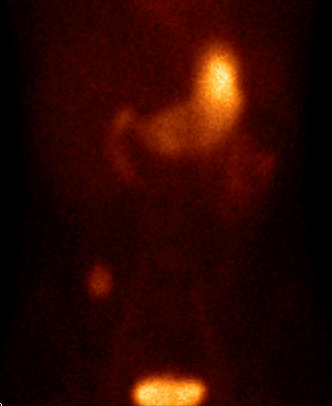

Among the general characteristics of isotope examinations, besides the ability to gain functional information, it is important to mention that – derived from the tracer principle – the examinations are highly sensitive, so the pathological processes can be detected at an early stage. SPECT is able to detect nano-molar radiotracer concentrations, while PET picks up signals coming from pico-molar radiopharmaceutical quantities. The higher sensitivity is due to the fact that functional alterations of metabolism usually precede detectable morphological changes of the tissues, thus functional studies allow earlier and more precise diagnostics. Another aspect of higher sensitivity is that in an optimal scenario, the biologic contrast between normal and pathologic function is very high. Therefore, signal intensity of a normal tissue process will be much lower than that of a pathologic one, making them easily distinguishable on the image. (Figure 2.)

Test iframe

2. FDG PET Maximum Intensity Projection (MIP) image. There is a large biological contrast between the normal and the pathologic tissues. Right sided breast cancer, ipsilateral metastatic lymph nodes and multiplex metastases in the lung. Physiologically elevated FDG uptake is seen in the brain, salivary glands, tonsils, liver and the spleen as well as in the bone marrow and at certain segments of the intestines. Also, there is increased FDG activity in the kidneys and the urinary bladder due to excretion.